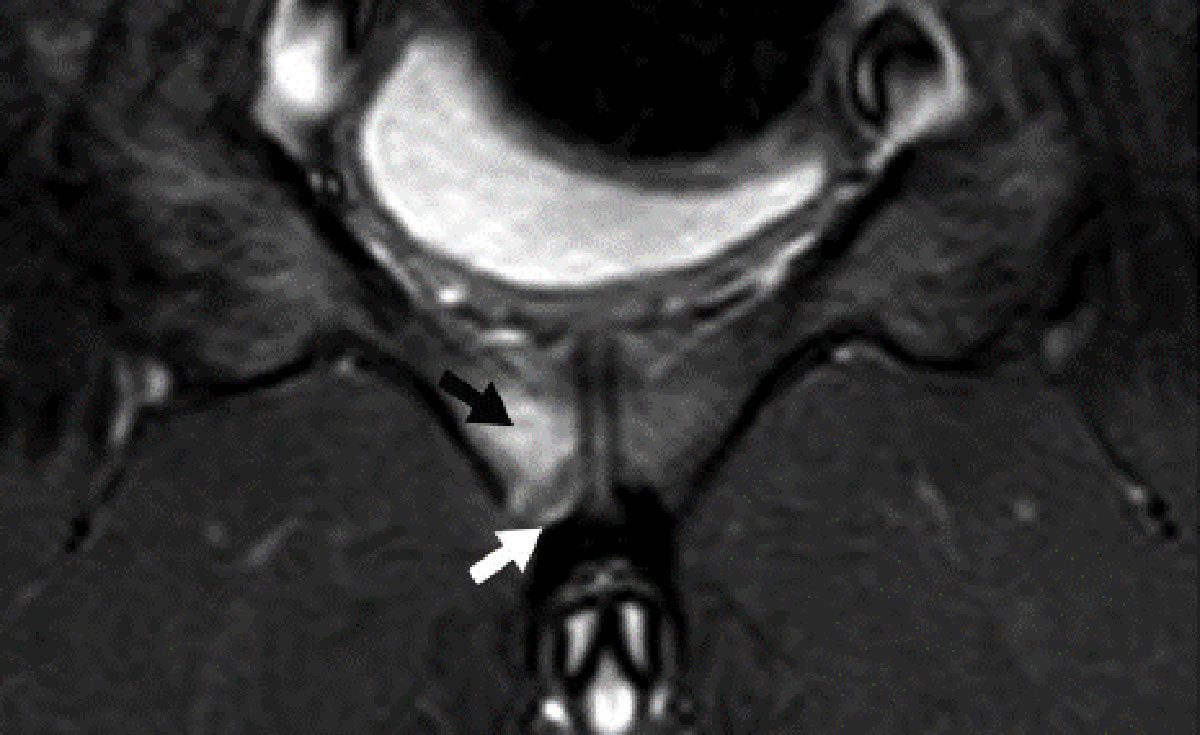

Ein 30-jähriger Eishockeyspieler klagte über zunehmende Beschwerden im Bereich des vorderen Beckens nach Spielbelastung. Der Schmerz war insbesondere bei schnellen Antritten und Richtungswechseln vorhanden und strahlte zum Teil in beide Leisten. Die Hüftgelenke beidseits zeigten sich frei beweglich und schmerzfrei. Die eingeleitete MRT-Diagnostik zeigte eine Flüssigkeitsansammlung im Os pubis beidseits direkt an der Symphyse. Eine Adduktorenansatztendinitis, Cleft-Zeichen oder eine Leistenhernie waren nicht zu sehen. Der Athlet wurde für vier Wochen aus der sportlichen Belastung genommen. Zudem wurde eine Stoßwellenbehandlung (fokussiert) und Physiotherapie durchgeführt. Ergänzend wurde eine orale Supplementation von Vitamin D3 und Calcium eingeleitet sowie eine medikamentöse Therapie mit Ibandronat. Hierunter besserten sich die Beschwerden und der Patient konnte nach vier Wochen wieder schmerzfrei in das Aufbautraining zurückkehren.

Die Symphyse und die Adduktoren an der Innenseite des Oberschenkels sind bei Eishockeyspielern eine häufige Verletzungslokalisation, da sie beim Skaten, bei den vielen seitlichen Bewegungen, Schüssen und dem Abbremsen des Körpers stark beansprucht werden. Die Symphysenregion hat in der Medizin in den letzten Jahren große Aufmerksamkeit erhalten [6]. Problem dieser Schmerzlokalisation ist, dass mehrere Verletzungen, teils völlig unterschiedlicher Genese, dahinterstecken können [7, 8]. Neben der Leistenhernie (Sportlerleiste) ist eine Ansatztendinitis der Adduktorenmukulatur häufig zu finden [9]. Nicht übersehen sollte man allerdings auch das Secondary Cleft Syndrom, bevor man eine klassische Symphysitis diagnostiziert. Bei der Verletzung im Rahmen eines Cleft-Syndroms kommt es zu einer Spaltbildung zwischen dem Schambeinknochen und der dort ansetzenden Adduktorenmuskulatur [8, 10]. Das Superior-Cleft- und das Secondary-Cleft-Syndrom unterscheiden sich lediglich hinsichtlich der Region, in der der Spalt zwischen dem Knochen und der Muskulatur auftritt. Die Ursachen dieser Cleft-Syndrome sind noch nicht endgültig geklärt. Als Ursache kommen neben einer Instabilität (Makro- und Mikroinstabilität) des Schambeinspaltes (Symphyse), chronische Überlastungen der Adduktorenmuskulatur mit erhöhter Zugbelastung am knöchernen Ansatz, aber auch akute Verletzungen nach einem Sturz auf das Becken in Frage [8]. Der Nachweis eines Cleft-Syndroms erfolgt in der MRT oder ergänzend in der Symphysographie [10]. Bei letzterer Untersuchung lässt sich das Ausmaß des Cleft-Syndroms und seine genaue Lokalisation darstellen. Die Therapie der Cleft-Syndrome ist weiterhin nicht vollständig standardisiert. Neben gezielten Injektionen in den Schambeinspalt mit z. B. ACP (autologes konditioniertes Plasma) gibt es auch die Möglichkeit der operativen Therapie. Ziel der Operation ist es, den Defekt zwischen dem Knochen und der Muskulatur zu schließen.